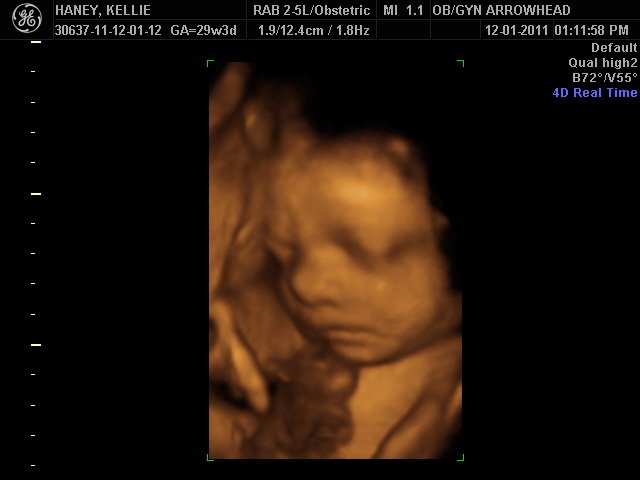

We offer complimentary 3D/4D Ultrasounds to all our OB patients around 30 weeks! The following photos are some examples of our work, shown with permission from our patients.